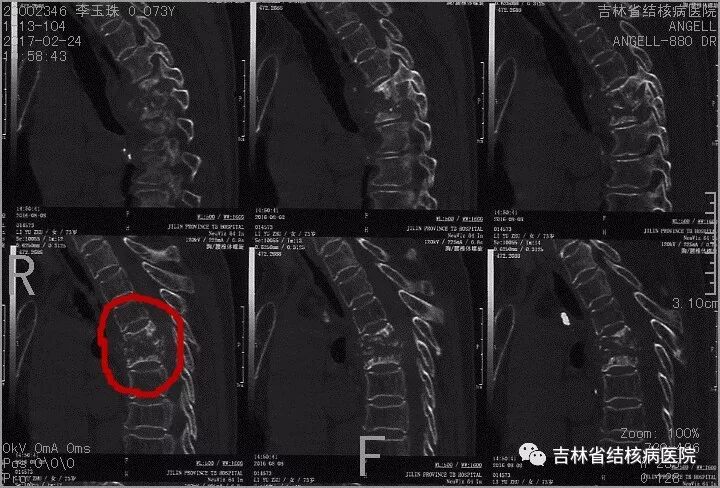

为了让大家更直观感知什么是骨结核,咱们看一张脊柱胸椎5、6结核的三维CT。